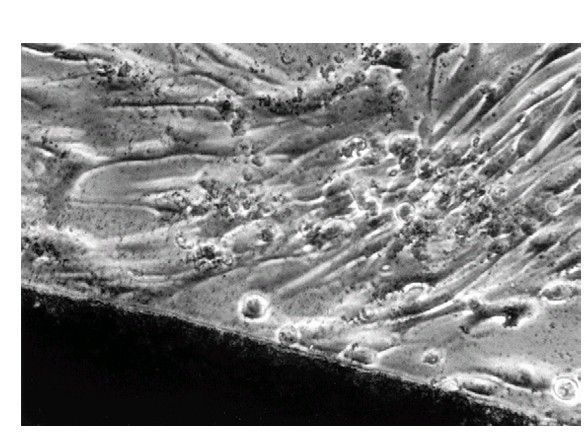

. Light microscopic view of a noncytotoxic interaction between a material (dark image at bottom of the picture) and periodontal ligament fibroblasts in a cell culture (in vitro) test. The morphology of the f ibroblasts indicates that they are alive and are not suffering from a toxic response (see Figure 6-3 for contrast). The material in this case was a calcium hydroxide pulp-capping agen